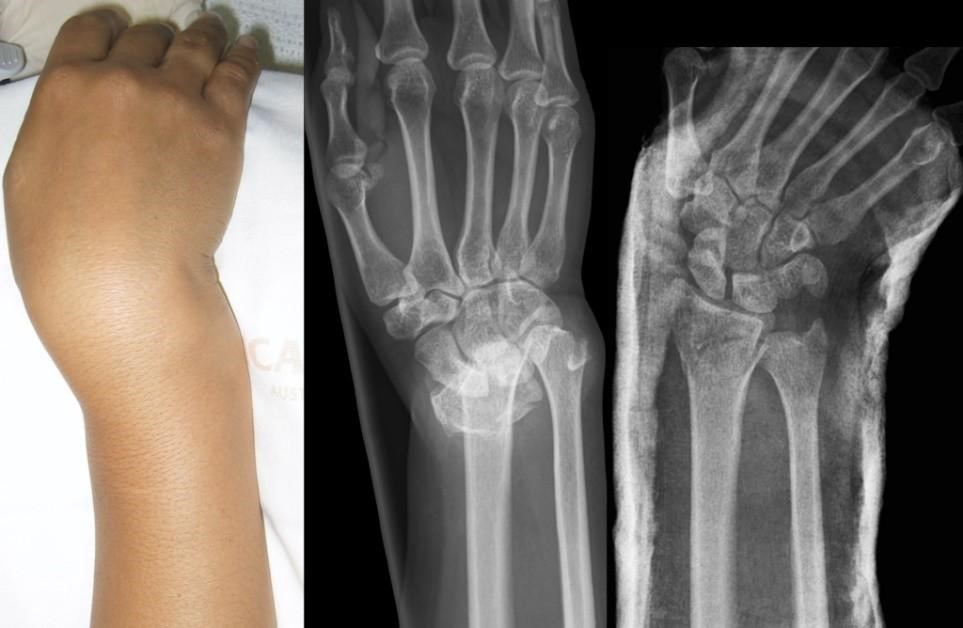

شکستگی کالیس بیشتر در افراد بالای ۴۰ سال، خصوصا زنان با پوکی استخوان رخ می‌دهد. در این آسیب، قطعه شکسته شده به سمت پشت و بیرون حرکت می‌کند و مچ حالت «چنگالی» پیدا می‌کند.

درمان اولیه معمولاً جااندازی بسته و گچ‌گیری است.

اما در مواردی که جابجایی شدید باشد، شکستگی خرد شده باشد یا گچ قادر به نگه‌داشتن استخوان نباشد، جراحی با پین‌گذاری، فیکساتور خارجی یا پلاک ضروری است.